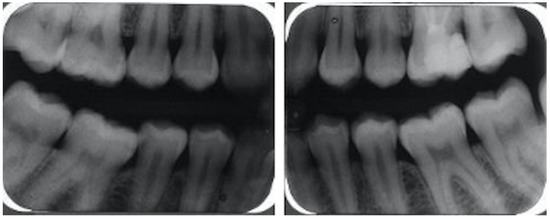

2. Case Report

2.3. Oral Examination